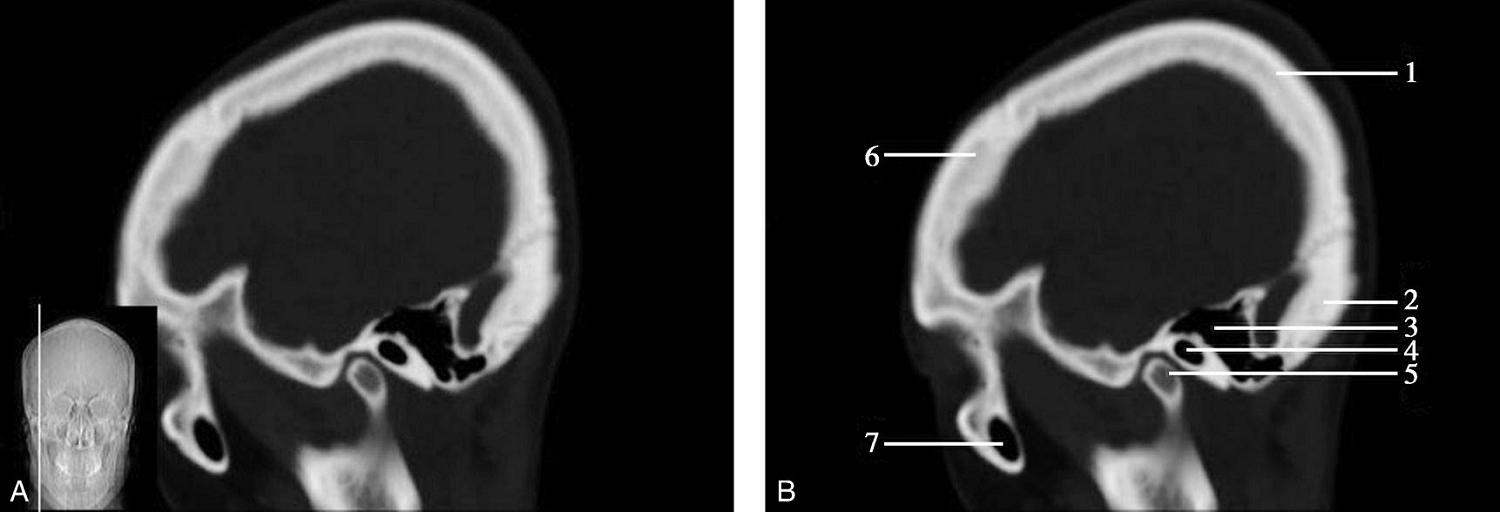

图1-2-2 颅底层面(骨窗)

A.横断面;B.横断面标注

1.鼻骨;2.筛窦纸板;3.颧骨眶突;4.翼腭窝;5.蝶骨大翼;6.卵圆孔;7.破裂孔;8.颞骨颧突;9.棘孔;10.斜坡;11.颞骨岩部;12.乳突;13.颈静脉孔;14.枕乳突缝;15.枕骨;16.枕内隆凸

层面前部呈开口向前的“V”字形,正中为鼻中隔,向两侧依次为筛窦和眼眶,眼眶内前部为眼球,后部为眶脂体。翼腭窝位于眼眶后部,窝内含有脂肪并有上颌神经通过。层面中部为蝶骨体,蝶骨体中部可见含气蝶窦,蝶窦后方为枕骨基底部,两者呈前后关系,其上面构成斜坡。蝶窦两侧为蝶骨大翼,其后外侧缘处由前向后可见卵圆孔和棘孔,分别有下颌神经和脑膜中动脉通过。斜坡外侧、岩骨尖前方为破裂孔。蝶骨大翼与眶外侧壁的颧骨借颧弓相连,颧弓和蝶骨大翼之间有咬肌及颞肌。层面中部外侧为外耳道。颞骨岩部呈“八”字形,相互之间借破裂孔软骨、蝶岩软骨结合和岩枕软骨结合连接。岩部后外侧的乳突部内可见乳突小房,乳突部与枕骨相接。岩骨后部可见颈静脉孔,内有颈内静脉、舌咽神经、迷走神经和副神经通过。层面后部为颅后窝,其内可见延髓,延髓前方为延髓前池,内有椎动脉,后外侧为小脑半球下部,后方为第四脑室、小脑扁桃体及小脑蚓部。

破裂孔、卵圆孔、棘孔及斜坡等均为重要的解剖结构,临床常见疾病如鼻咽癌常侵犯上述结构(图1-2-3)。颈静脉孔区较常见的肿瘤为颈静脉球瘤,常伴有颈静脉孔及其邻近骨质的破坏(图1-2-4)。